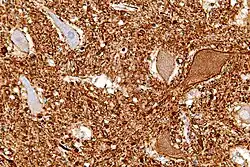

Central chromatolysis

Central chromatolysis is a histopathologic change seen in the cell body of a neuron, where the chromatin and cell nucleus are pushed to the cell periphery, in response to axonal injury.[1][2] This response is associated with increased protein synthesis to accommodate for axonal sprouting. In addition to traumatic injuries, central chromatolysis may be caused by vitamin deficiency (pellagra[3]).